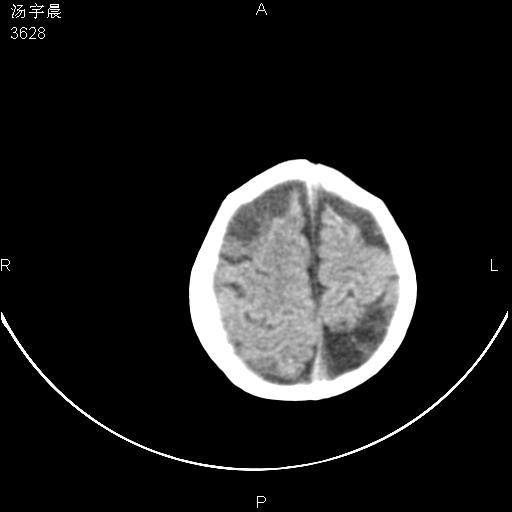

早产儿,现两月大,2月份在某医院诊断病毒性脑炎并治疗,mri报右颞部脑白质片状长t2信号,脑白质模糊。其他不详,现家属要求ct复查 。

双侧大脑半球大片状低密度,无明显占位表现, 符合病毒性脑炎。

小儿病毒性脑炎ct表现缺乏特异性,但其定位分布有一定特异性,单纯疱疹病毒性脑炎ct表现以颢叶病变为主,同时可累及其他脑区或伴出血,乙型脑炎表现为基底及丘脑的病变,流行性腮腺病毒性脑炎则ct表现可正常,故ct检查对病毒性脑炎的定性有重要的价值。 本例支持:病毒性脑炎的后遗改变!